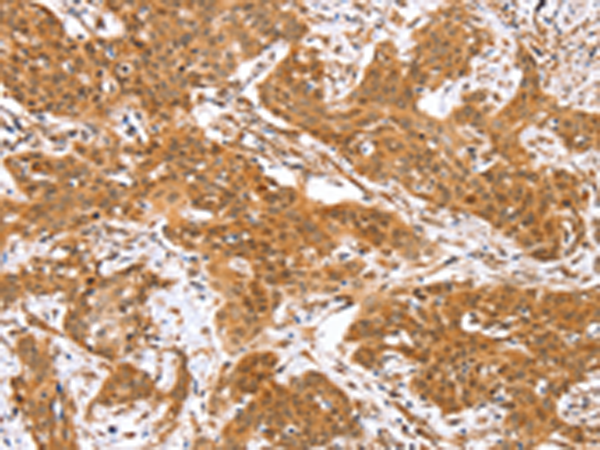

分类: 科研抗体货号: P01737别名: RISC; HSCP1应用: WB,IHC反应种属: Human, Mouse, Rat